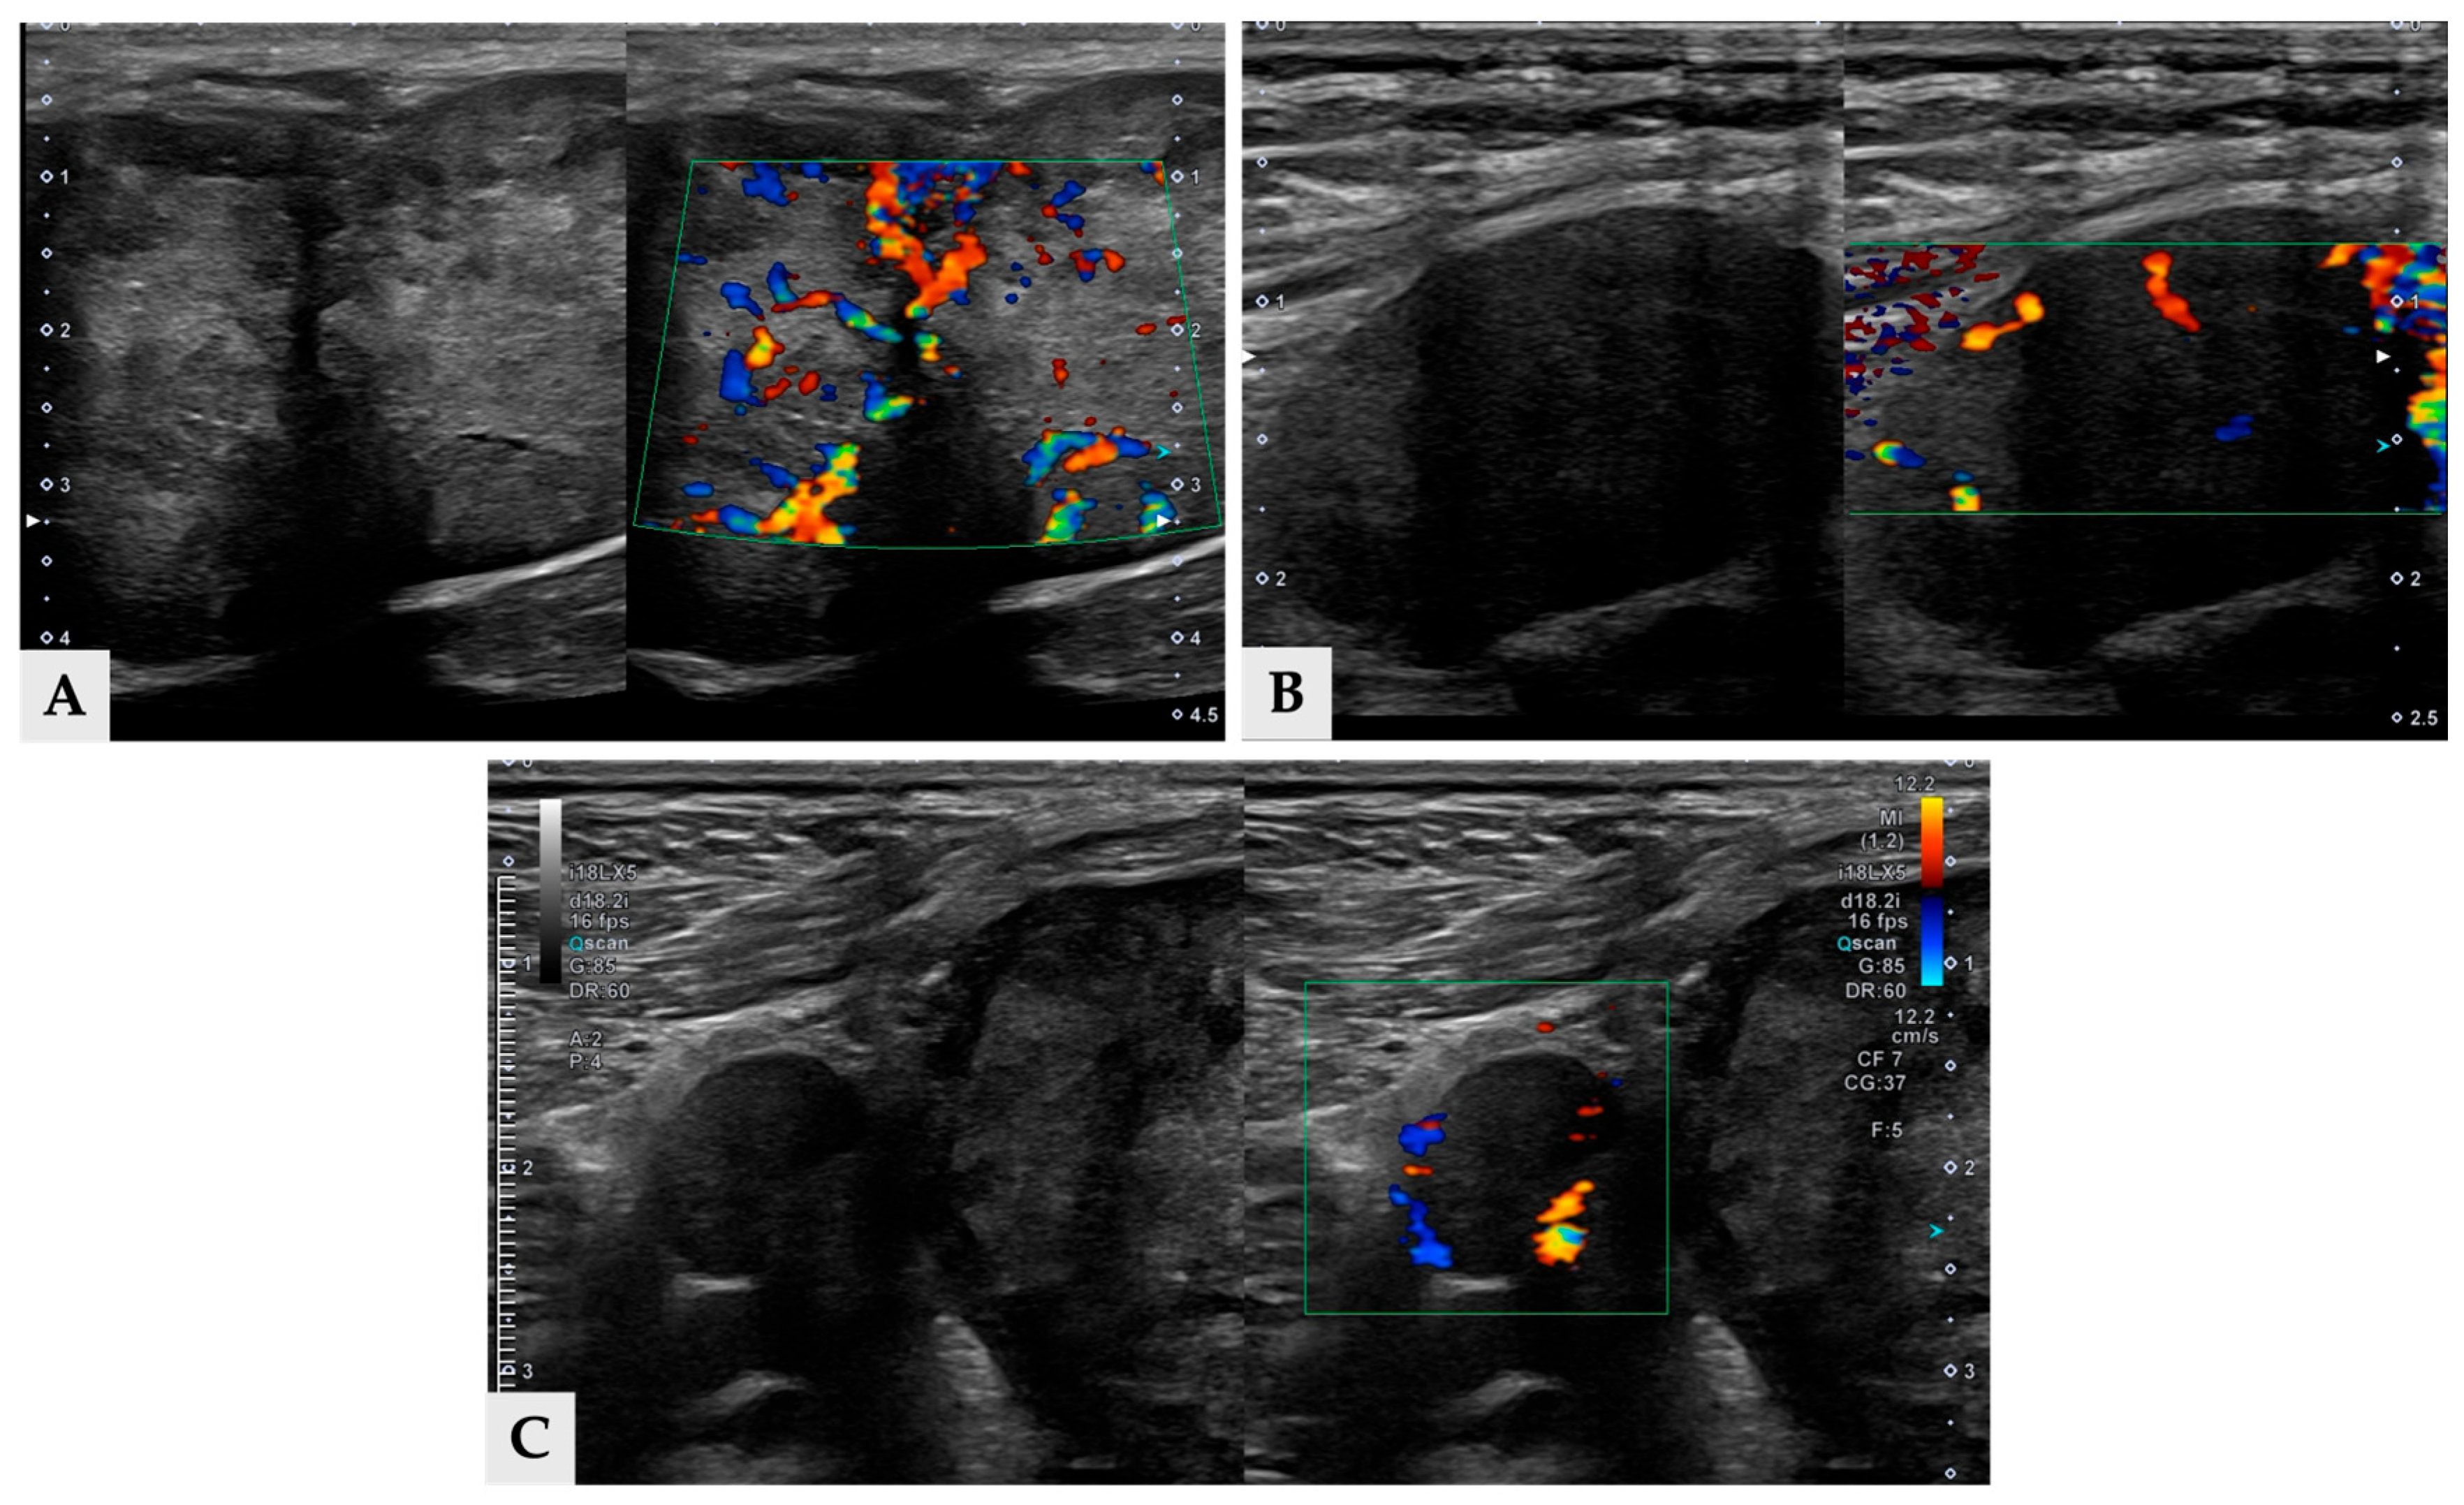

Multiple hyper- and hypoattenuating hepatic nodules were scattered throughout the liver parenchyma (maximum size 11.4 mm × 11.9 mm × 10.8 mm) (Figure 3), and numerous small splenic nodules exhibiting on pre-contrast and portal phase were also observed (Figure 4). Additionally, a soft-tissue mass was detected at the esophagogastric junction. Cervical ultrasonography revealed three distinct, heterogeneous right thyroid masses, with the largest mass demonstrating prominent vascularity on Doppler evaluation (Figure 5).

Figure 5.

Split view ultrasonographic images of three thyroid masses (A) Longitudinal ultrasound image of mass 1 demonstrating heterogeneous large mass with irregular internal echotexture (left), color Doppler image of mass 1 showing prominent vascular signals (right). (B) Longitudinal ultrasonographic image of mass 2, which is located cranial to mass 1, revealing a well-defined, hypoechoic mass. (C) Longitudinal ultrasound image of mass 3 which is between 1 and mass 2, with small round, hypoechoic mass.